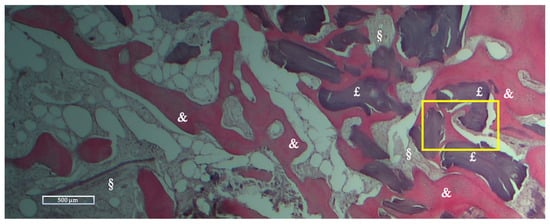

Histologic and Histomorphometric Results

| NFB | RB | SF | |

|---|---|---|---|

| Mean % ± Std dev | 28.27 ± 10.62 | 10.39 ± 12.01 | 61.33 ± 12.08 |

| Range % (Min-Max) | 16.51–59.74 | 0–36.89 | 40.26–75.59 |